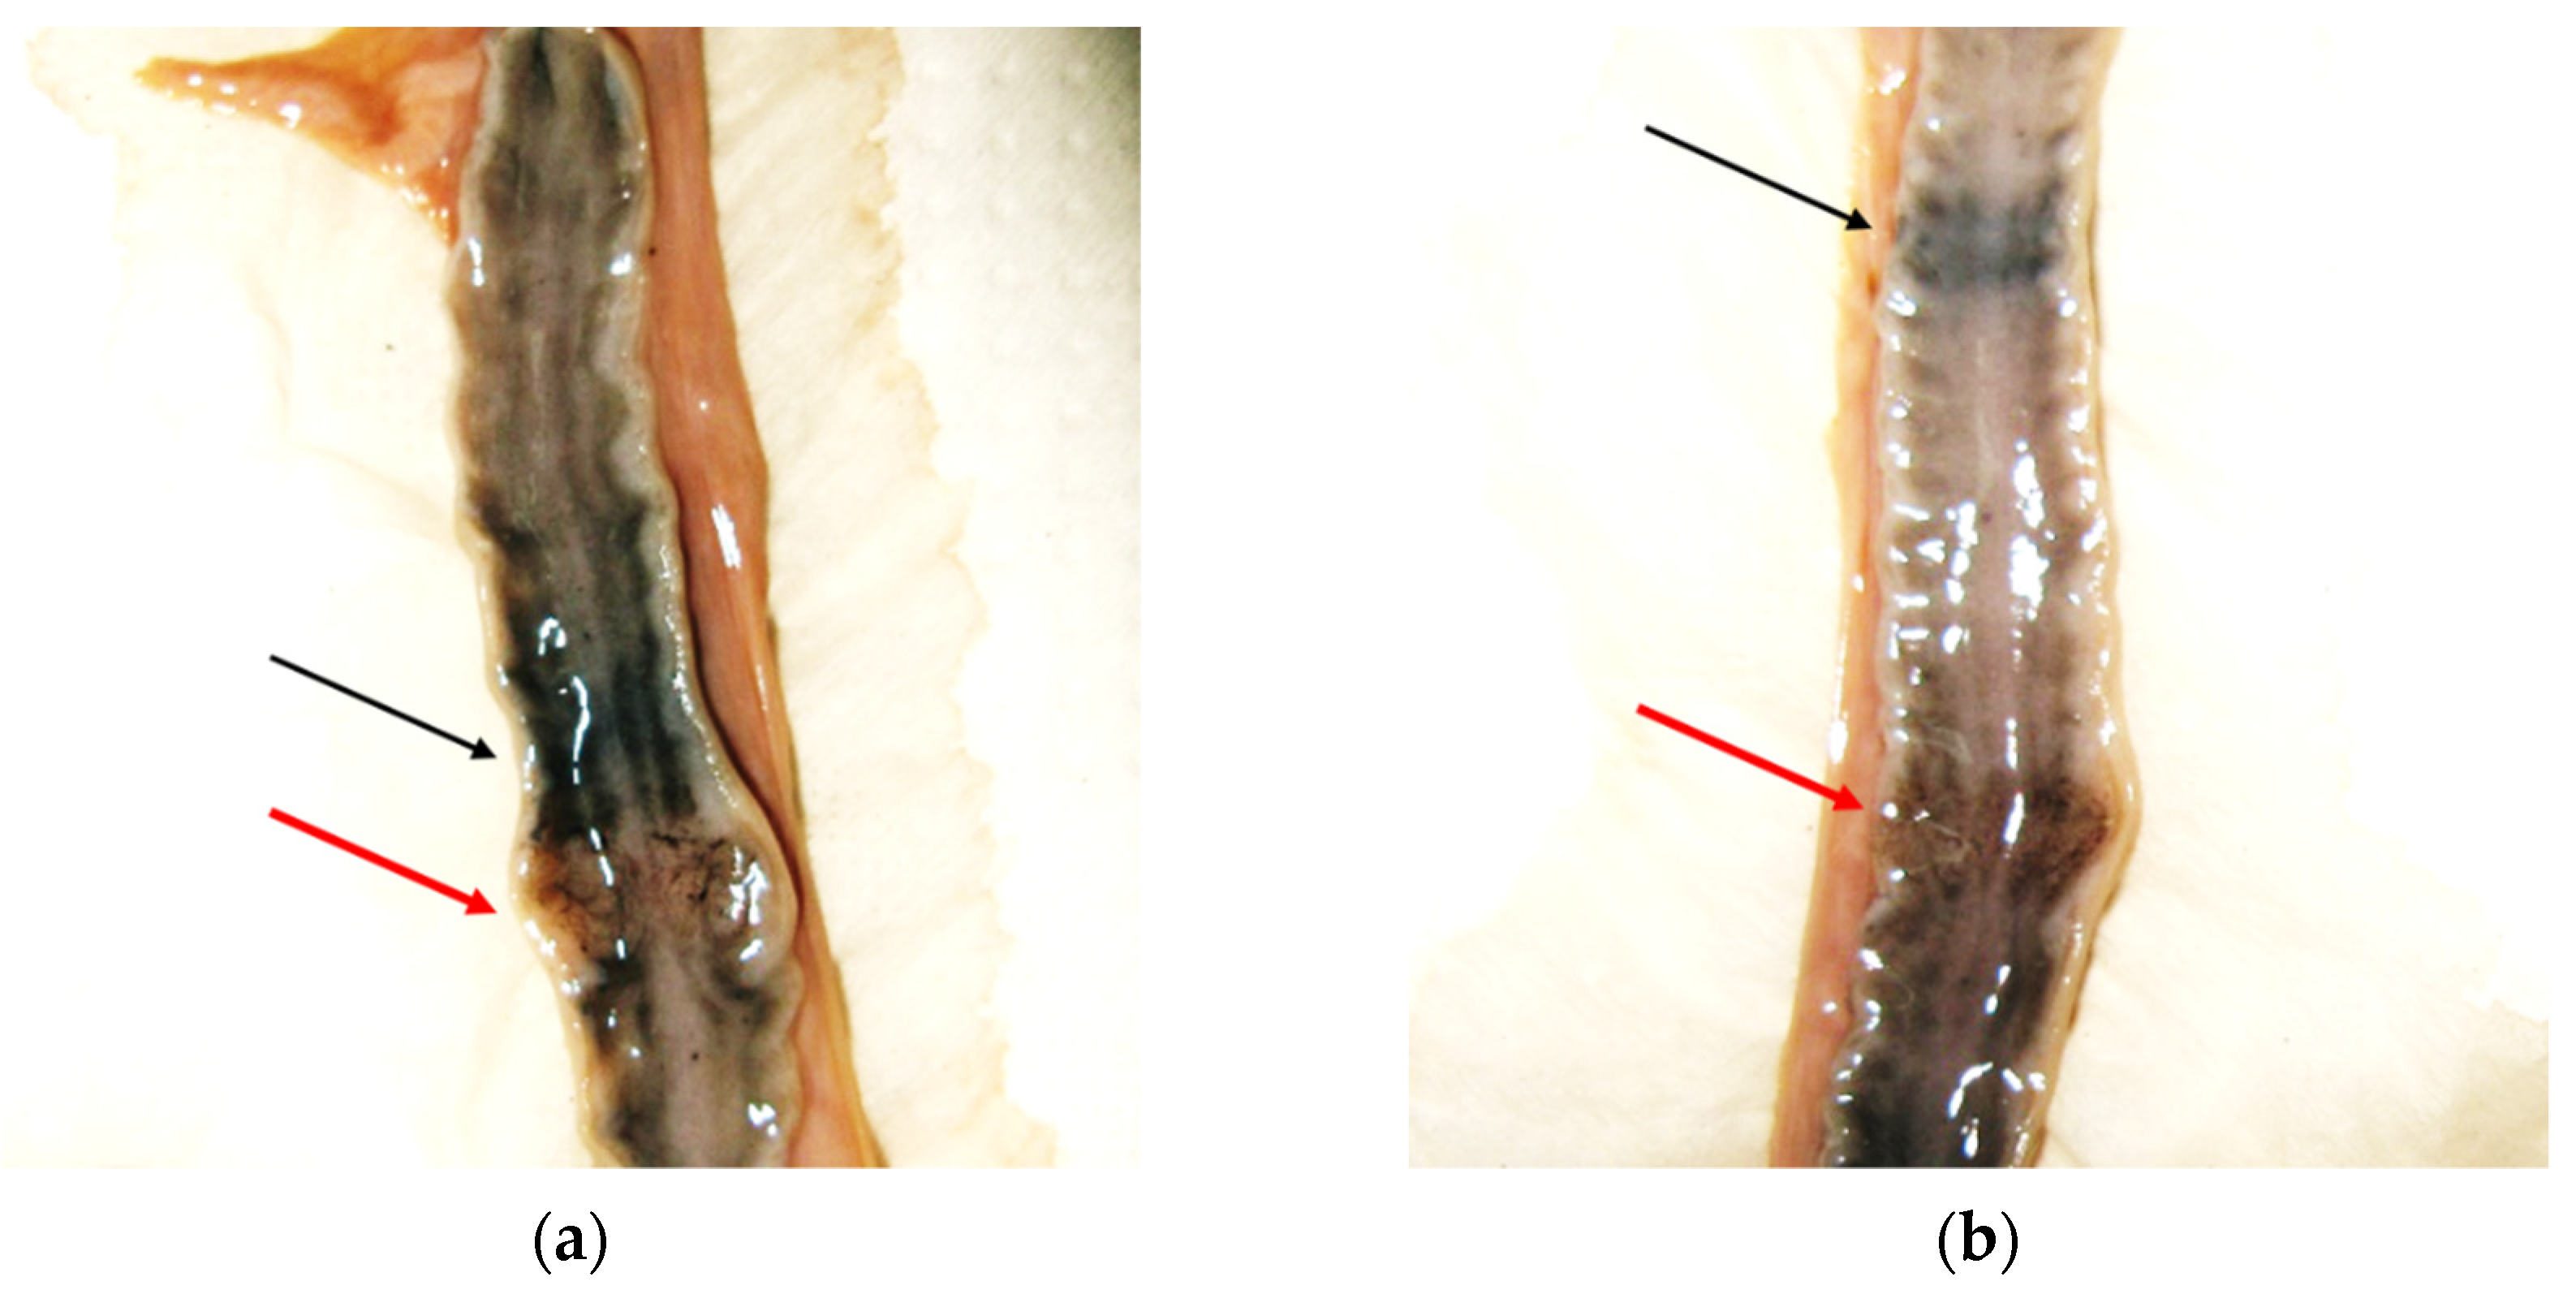

| Respiratory system | Adiaspiromycosis | 1 |

| Mineralized granulomas (unknown etiology) | 3 | |

| Mineralization foci in tracheal and bronchial cartilages | 13 | |